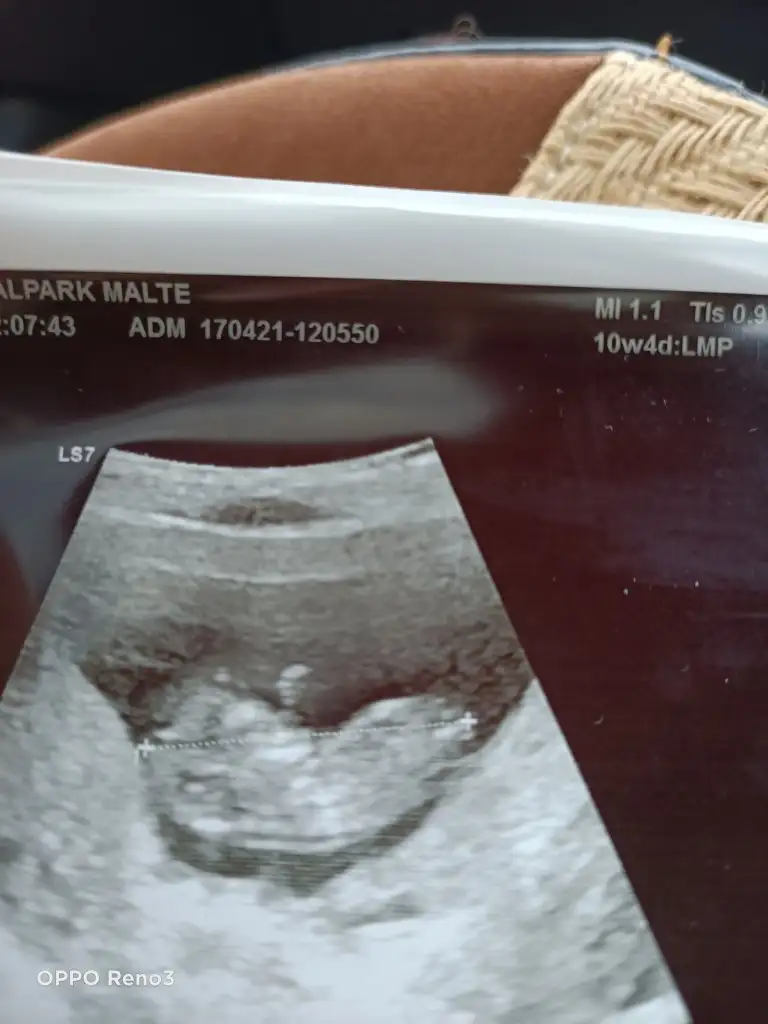

Gönlümden geçen kızdı ama erkek hissediyordum hepÇook tatlı maşallahçok net çıkmış ağzı burnu

Maşallah canım ne guzel pozlar yakalamış doktorunErkekler biraz erken gösteriyor sanırım ,benimki de hafif önden gidiyor hayırlısı bakalım.Senin bir kızın vardı degil mi ? Gönlünden geçen neydi